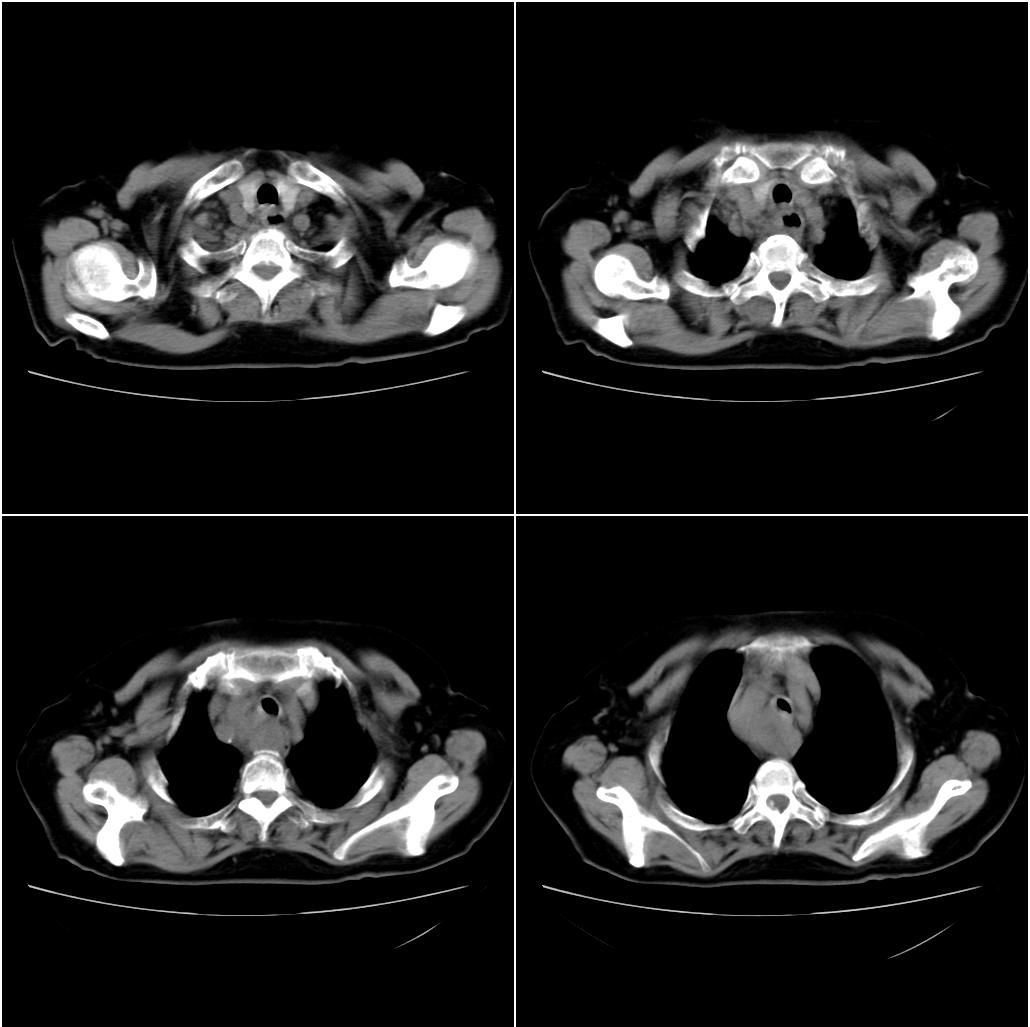

以下是引用sxlcbc在2007-12-23 4:27:00的发言:[br]气管源性肿瘤觉得有点不靠谱啊,看上去气管是受压改变的。更像是上段食管的改变,周围淋巴结肿大,食管受压。看看以下六幅图片:[br]不过,有一点不好理解:食管肿瘤应该有食道症状的,再说食管癌出现周围这么大的淋巴结也不多见啊,如果考虑淋巴瘤倒是更合理一点,这样气管,食管受压改变也许更合理一些。[br][br]